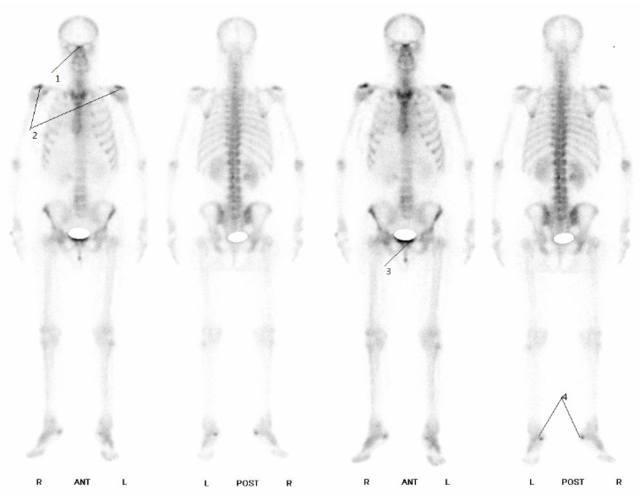

全身骨扫描报告解读一

骨扫描

全身骨扫描

骨扫描图片

骨扫描骨转移报告图

正常骨扫描图片

全身骨扫描图片

骨扫描显示骨转移图片

骨扫描图片怎么看